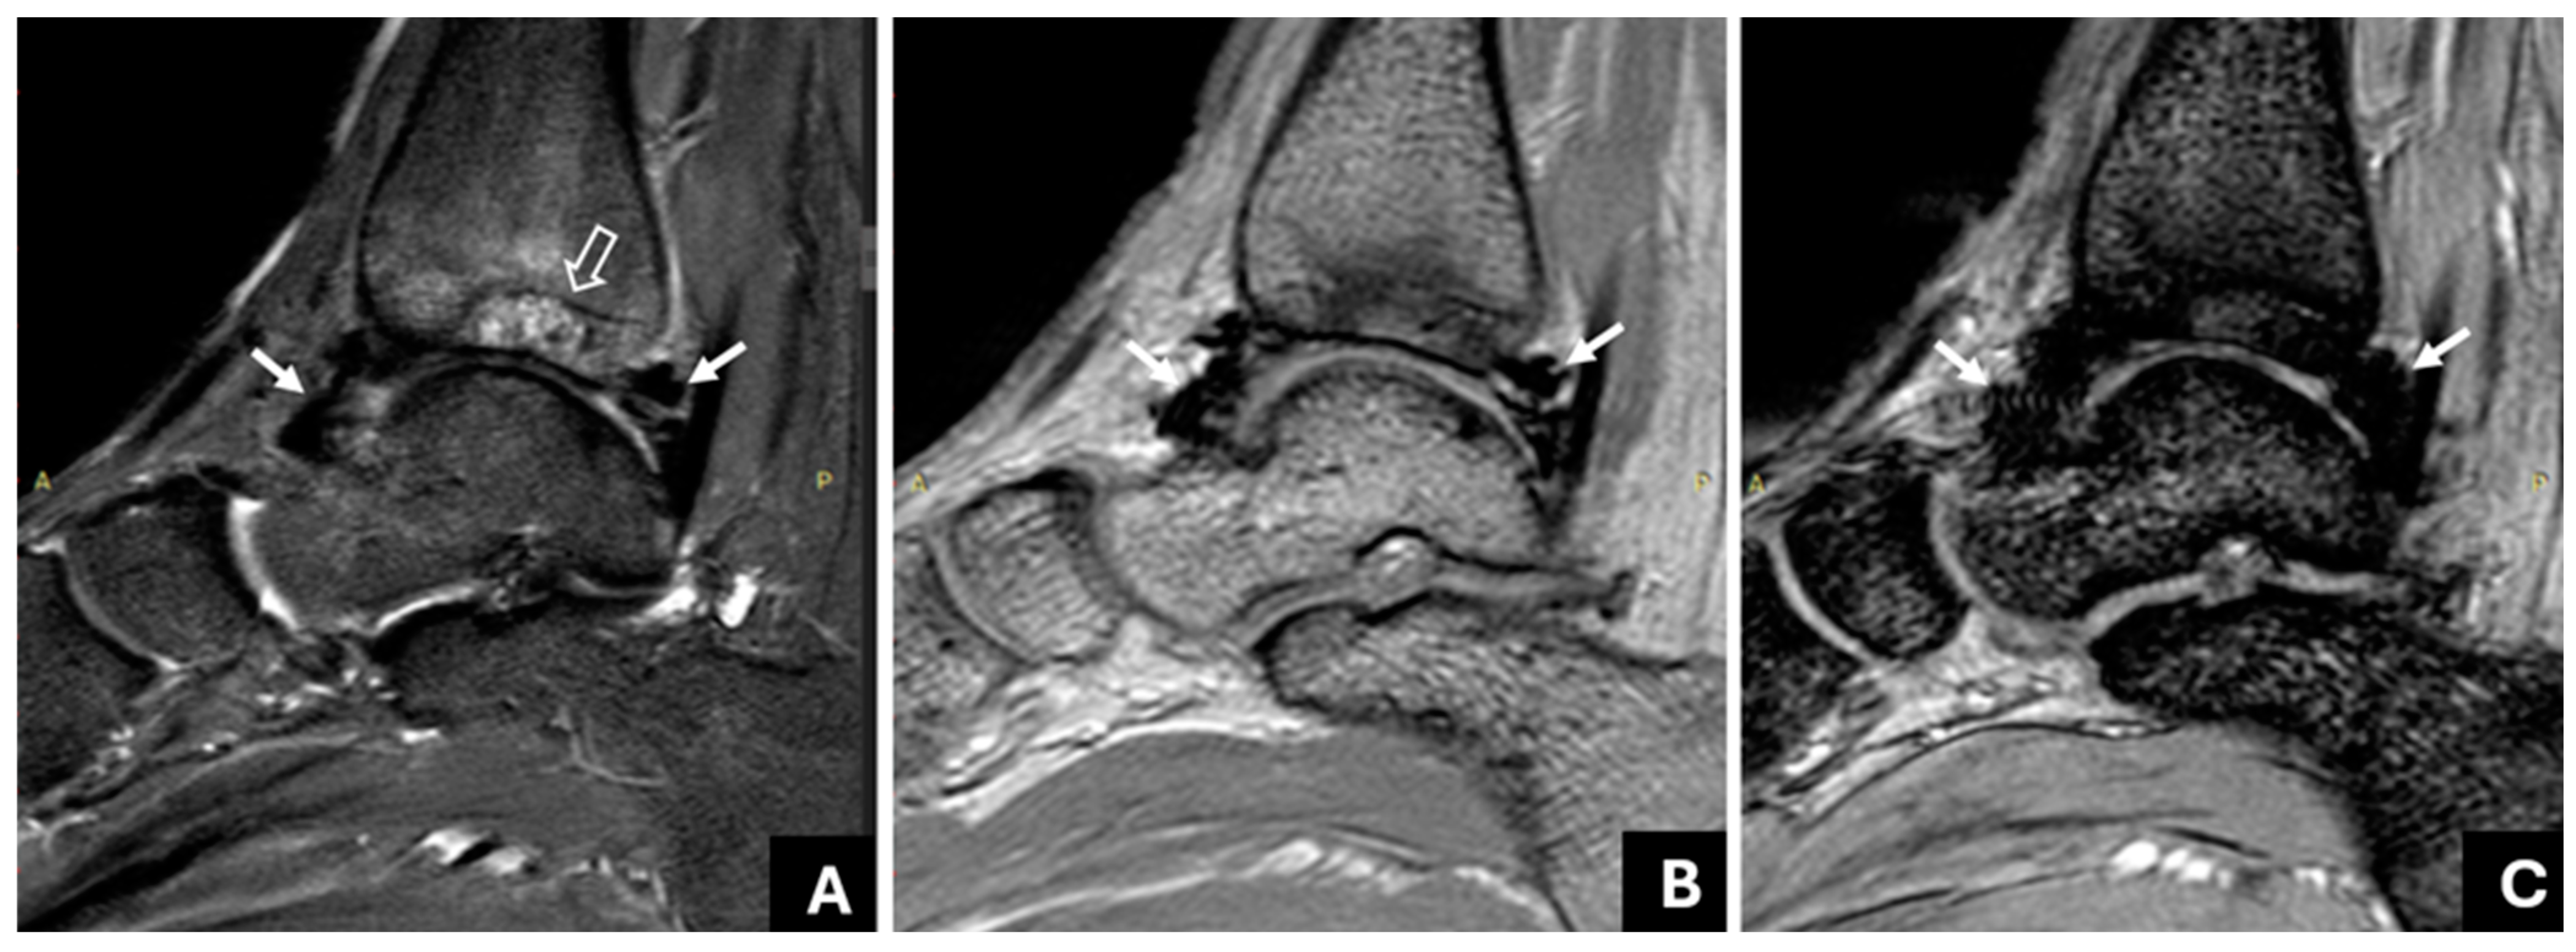

3.1. Detection of Joint Hemosiderin Deposition with mGRE Sequence: Inter-Reader Agreement

3.2. The Association of Joint Hemosiderin Deposition with Synovial Thickening, Effusion, and Osteochondral Changes (OCC)

3.3. Association of Joint Hemosiderin Deposition with the Number and Chronicity of Joint Bleeds and Clinical Score